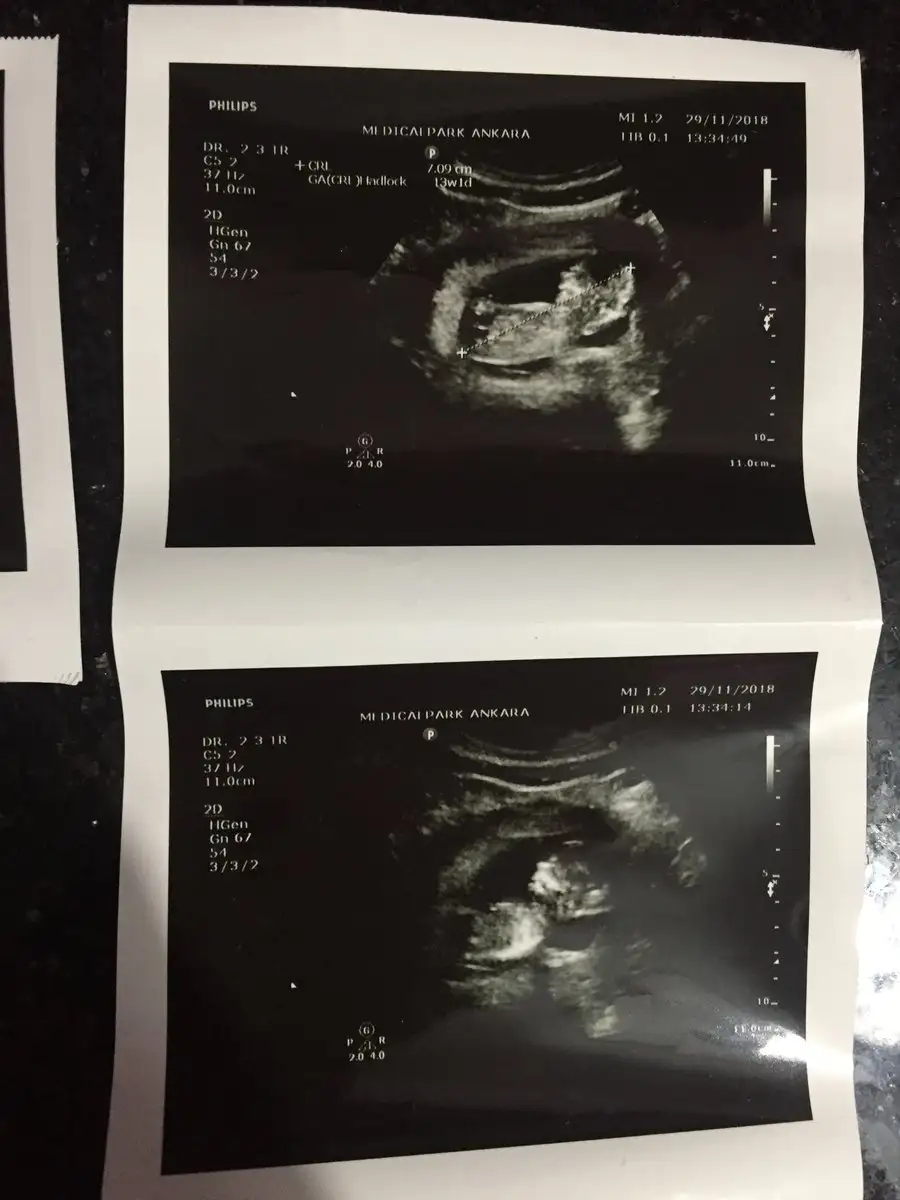

Ben bugün 12. Haftayı doldurmuşken ayrıntılı ultrasona girdim organlar ölçümler herşey çok iyi dedi drum

İkili taramayı önermiyor fala bakmakdan farklı değil diyor fetal DNA yaptırın dilerseniz ama ölçümler çok normal baktırmasanızda olur dedi